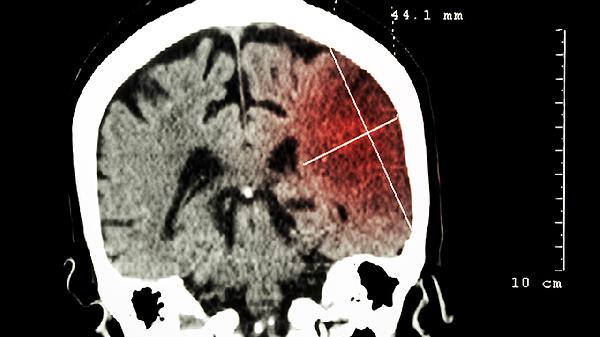

5、影像学检查

医生可能根据情况安排头颅超声或CT。婴幼儿前囟未闭合时,超声可初步筛查颅内出血。CT能明确颅骨骨折及出血量,但需权衡辐射风险,通常用于严重外伤评估。